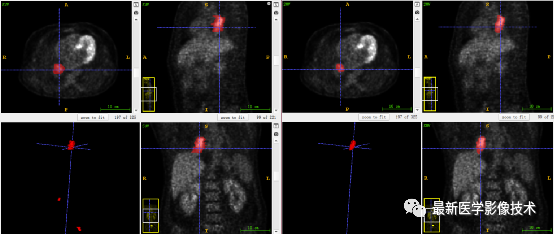

7、验证集分割结果:输入整个图像通过滑窗叠加预测结果,左图是金标准,右图是预测结果